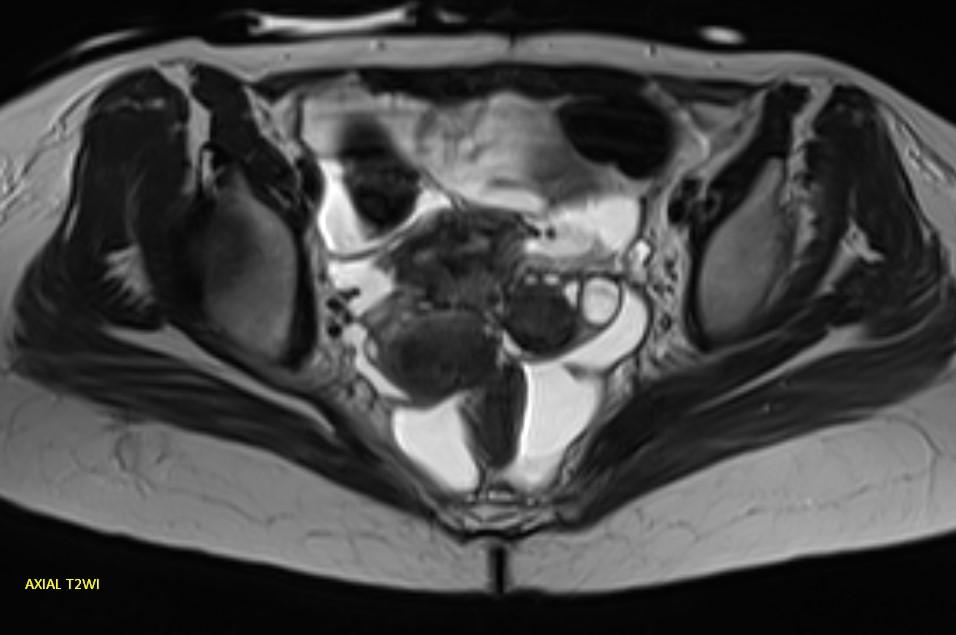

*23-year-old female with primary infertility.

Answer: Kissing Ovary Sign

MR images demonstrating the kissing ovaries, bilateral endometriomas (chocolate cysts), and peritoneal inclusion cyst (peritoneal pseudocyst).

Blood products in ovaries may cause adhesions to pull the ovaries toward the midline. This is considered a sign of pelvic endometriosis (1).